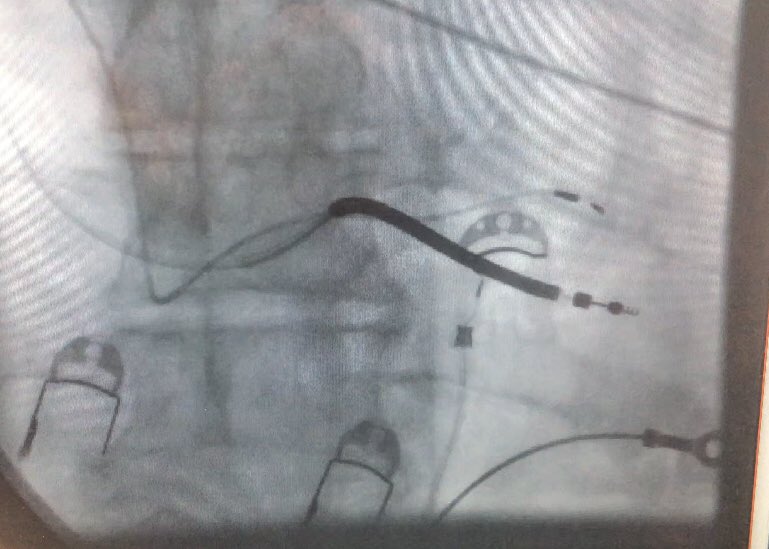

Our first *3* implants in the @AbbottCardio #ASCEND trial yesterday! The lead handles beautifully and we got fantastic LBB capture in all patients. #EPeeps #DontShocktheHis 😂😂